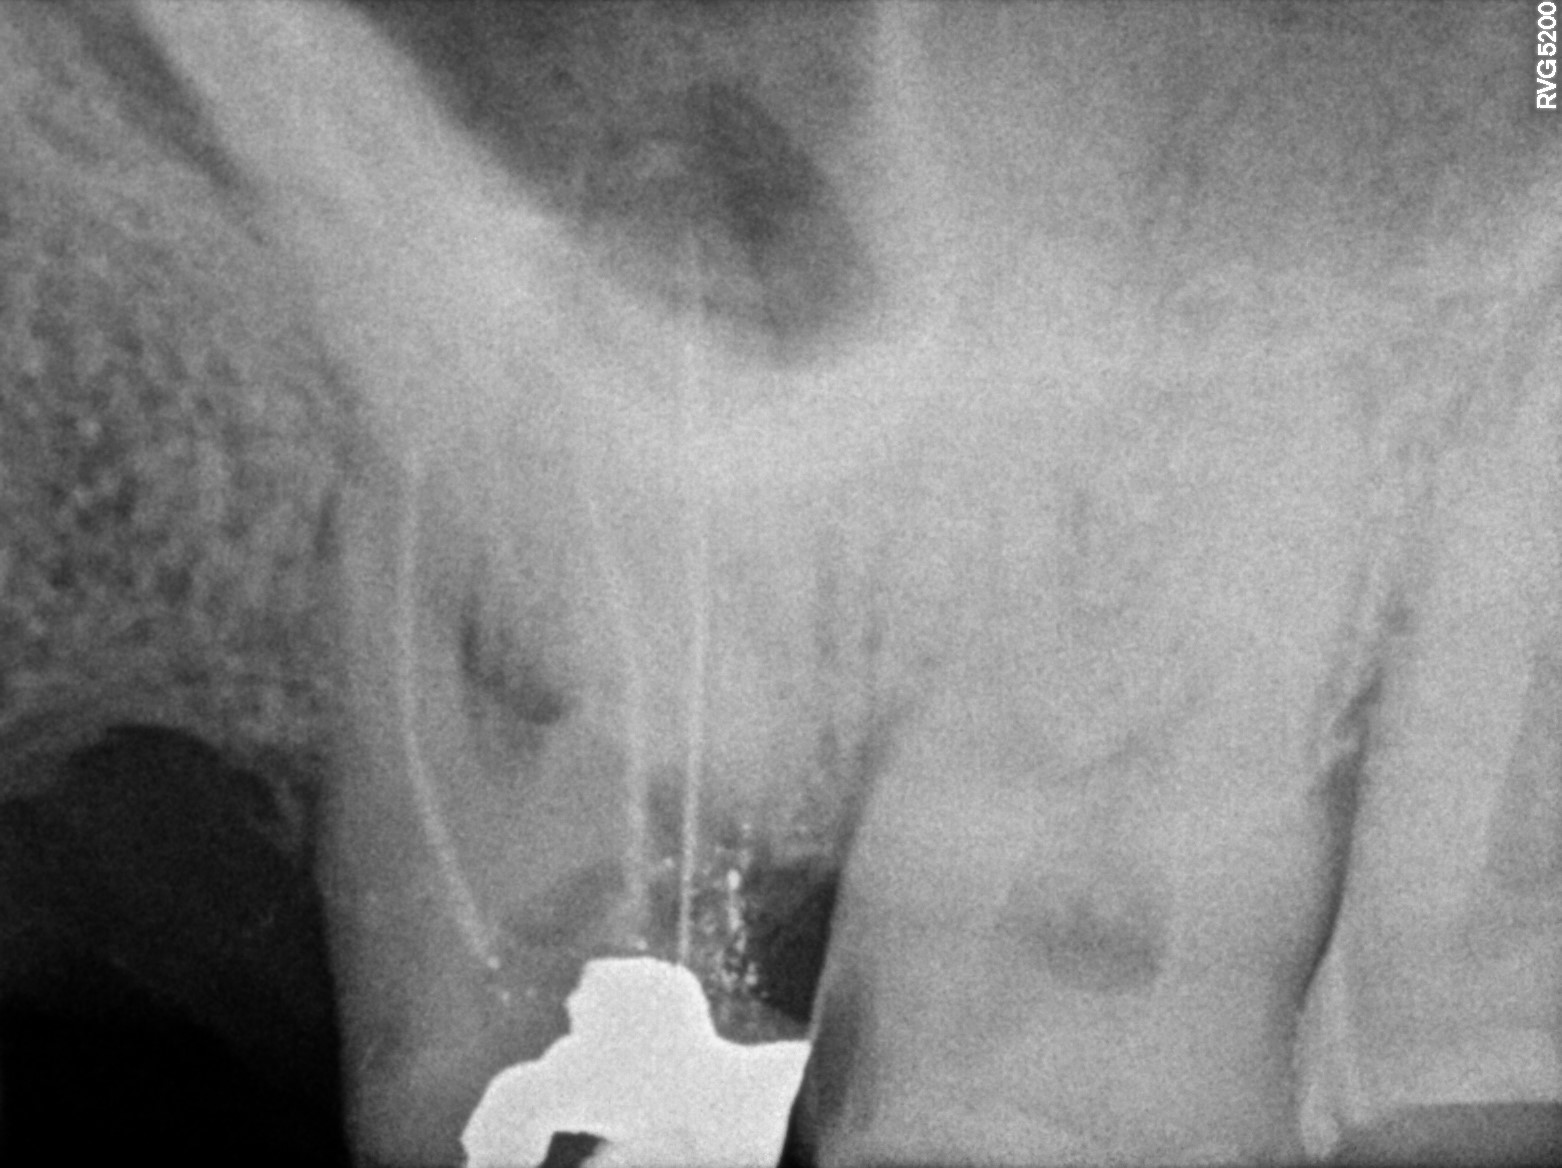

Dental Radiographs FHIR: DocumentReference · LOINC 24641-7

xray_1773475755_1.jpg

24641-7